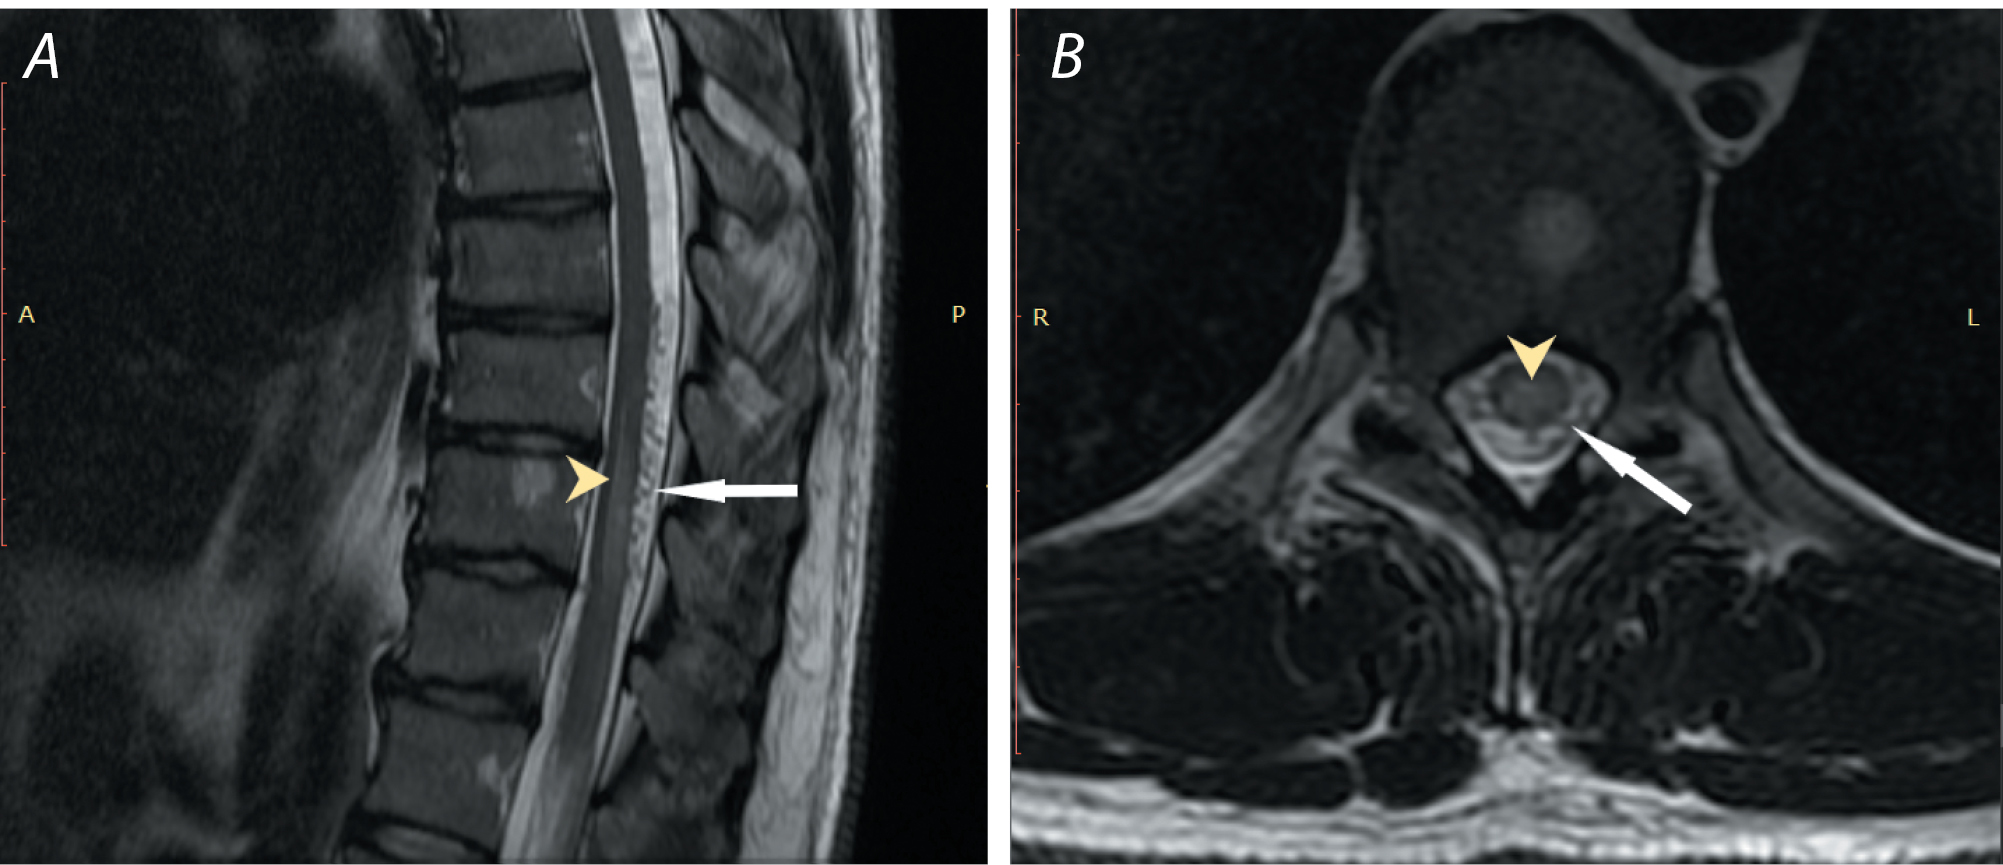

В отдельных ситуациях слабовыраженного коллатерального кровоснабжения СМ ишемический очаг может затрагивать только серое вещество передних рогов ввиду большей чувствительности мотонейронов к аноксии, а также наличия зоны «водораздела» между пиальными и сулькокомиссуральными артериями. Данная патоморфологическая картина со временем приводит к характерной аксиальной МР-картине по типу «глаз совы» или «глаз змеи» с двусторонней гиперинтенсивностью на Т2-ВИ [27, 31]. На сагиттальных Т2-ВИ такой гиперинтенсивный очаг имеет «штифтообразный» или «карандашеподобный» вид, затрагивая, как правило, более 2 позвоночных сегментов (рис. 2) [19].

Рис. 2. МР-исследование пациентки А. с артериальным инфарктом СМ на уровнях С2–С3, С3–С7.

A — Т2-ВИ, сагиттальная плоскость: многофокусный интрамедуллярный гиперинтенсивный очаг вытянутой формы на уровнях C2–C3, C3–C7, светло-жёлтой линией обозначен срез на уровне С3 (D), фиолетовой линией обозначен срез на уровне межпозвонкового диска С5–С6 (Е);

B — Т2-STIR, сагиттальная плоскость: многофокусный интрамедуллярный гиперинтенсивный очаг вытянутой формы на уровнях C2–C3, C3–C7;

C — Т1-ВИ, сагиттальная плоскость: многофокусный интрамедуллярный гипоинтенсивный очаг вытянутой формы на уровнях C2–C3, C3–C7 (белые стрелки);

D — Т2-ВИ, аксиальная плоскость: интрамедуллярный гиперинтенсивный очаг на уровне С3, занимающий область серого вещества (феномен «Hologrey», светло-жёлтая стрелка);

E — Т2-ВИ, аксиальная плоскость: интрамедуллярные гиперинтенсивные очаги на уровне межпозвонкового диска С5–С6 (феномен «глаз змеи», фиолетовые стрелки);

F — Т1-ВИ, аксиальная плоскость: интрамедуллярный гипоинтенсивный очаг на уровне С3 (белая стрелка).

Fig. 2. MR image of patient A. with arterial infarction of spinal cord at С2–С3, С3–С7.

A) T2-weighed image, sagittal plane: multifocal intramedullary hyperintense elongated lesion at C2–C3, C3–C7; the light-yellow line indicates the section at C3 (D), the purple line indicates the slice at the C5–C6 intervertebral disc level (Е);

B) Т2-STIR, sagittal plane: intramedullary hyperintense elongated lesion (white arrows) at C2–C3, C3–C7;

C) T1-WI, sagittal plane: multifocal intramedullary hypointense elongated lesion at C2–C3, C3–C7 (white arrows);

D) T2-weighed image, axial plane: intramedullary hyperintense lesion at C3 occupying the gray matter area (hologrey phenomenon, light yellow arrow);

E) T2-weighed image, axial plane: intramedullary hyperintense lesions at the intervertebral disc at C5–C6 (snake eyes phenomenon, purple arrows);

F) T1-WI, axial plane: intramedullary hypointense lesion at C3 (white arrow).